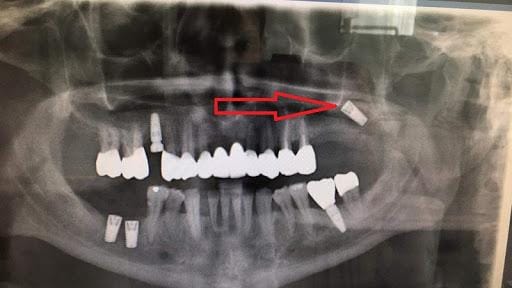

Inferior alveolar nerve injury

In the lower jaw, especially in the premolar and molar regions, there is an important structure within the bone called the inferior alveolar nerve canal. Inside this canal is the neurovascular bundle responsible for sensation of the lower lip, chin, and part of the cheek. If during drilling or implant placement the doctor does not accurately determine the safe distance from the nerve, the implant may contact, compress, or penetrate the canal.

The consequences of this complication can vary in severity. Mild cases may involve temporary numbness of the lip or chin for a few days or weeks. More severe cases may involve prolonged numbness, paresthesia, tingling, burning sensation, or neuropathic pain, significantly affecting daily life. In severe and late-treated cases, nerve damage may result in long-term sequelae or may be very difficult to fully recover.

It is important to note that this complication is not only due to “incorrect implant placement”, but can also result from inaccurate radiographic interpretation, incorrect distance estimation, or lack of precise placement technology. Therefore, this is a typical complication showing that Implant cannot be performed based on subjective estimation.

Maxillary sinus injury

In the upper jaw, especially in the molar and premolar regions, the maxillary sinus lies above the jawbone. After long-term tooth loss, the sinus tends to pneumatize downward, reducing the remaining bone height. If the doctor does not correctly assess bone height, or places the implant too deep, the implant may invade the sinus.

This complication may cause facial heaviness, sinus pain, chronic sinusitis, nasal discharge, or failure of osseointegration if infection occurs. In addition, when the implant enters or is too close to the sinus floor, prosthetic rehabilitation becomes more difficult, and sometimes the patient must undergo additional complex treatment procedures.